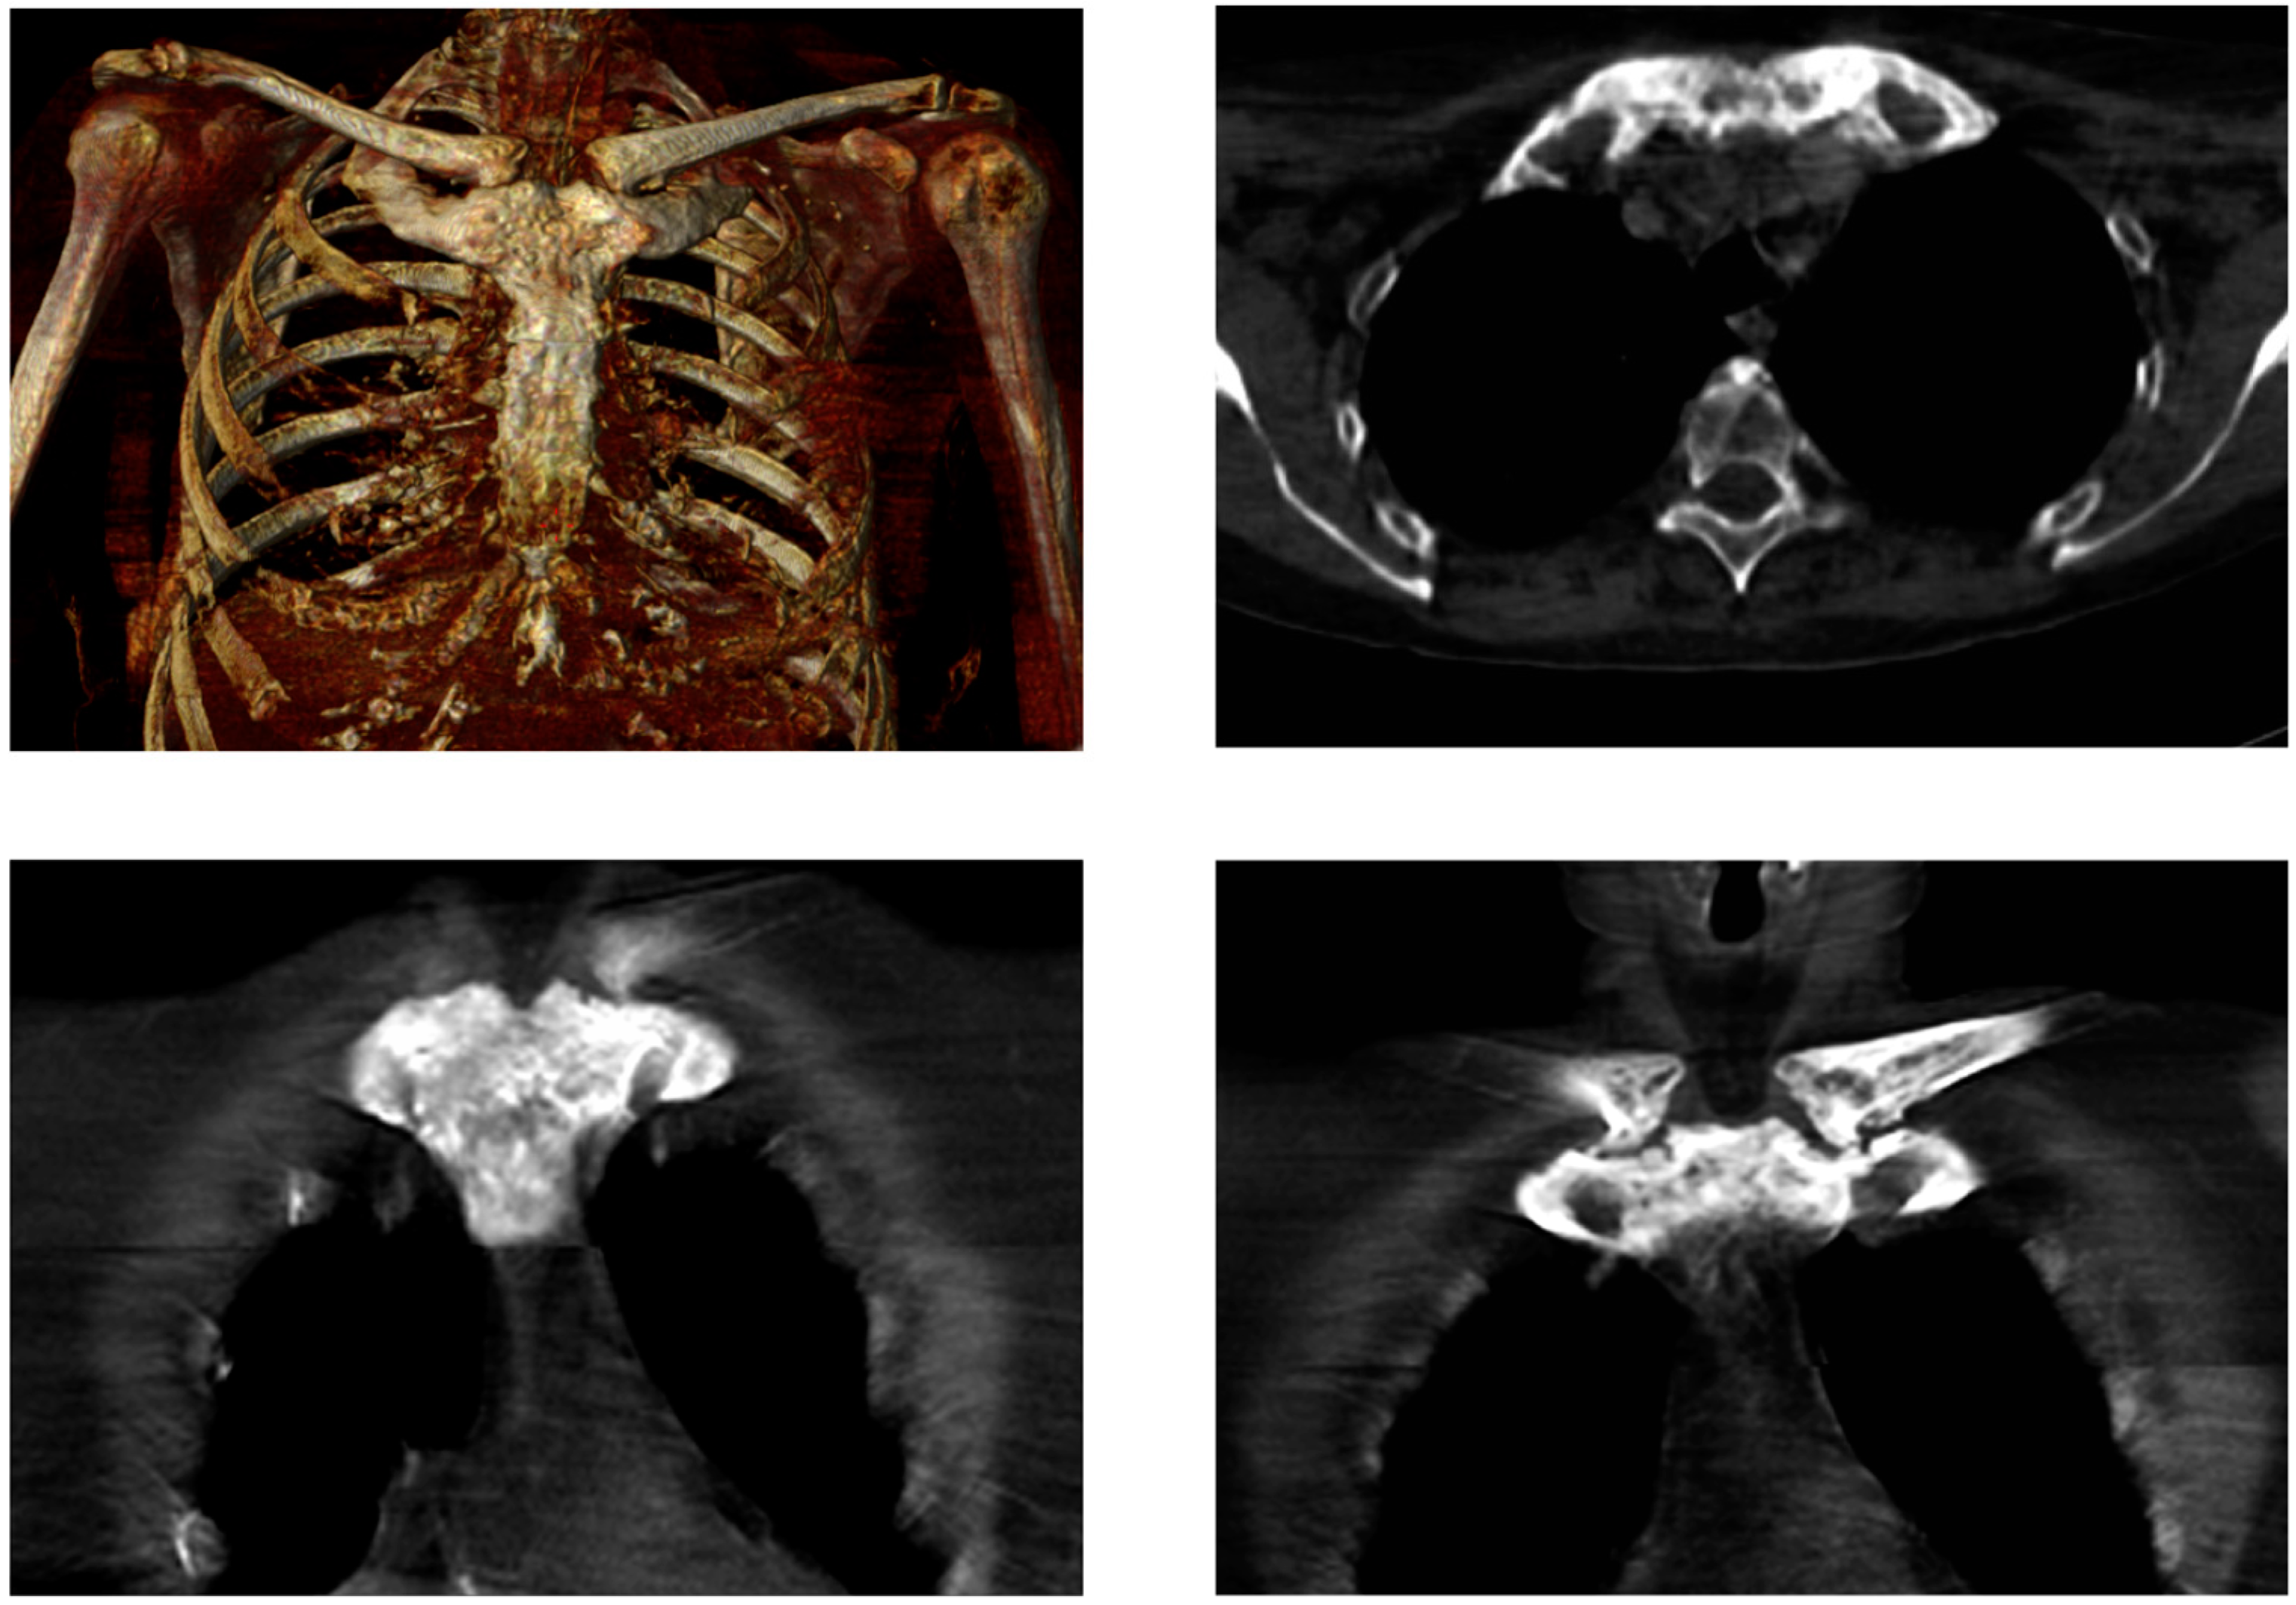

Figure 3. Low-dose CT, in line with bone scintigraphy (Figure 2, 2015) shows symmetrical hyperostosis of the sternal manubrium, medial parts of both clavicles, and anterior parts of the uppermost ribs. SCCH is a rare disorder typically starting with nonspecific inflammation of the sternocostoclavicular ligaments and the surrounding soft tissue. The disease is benign but chronic, and develops over several years, with progressive hyperostosis, fusion of the sternocostoclavicular joints, and soft tissue ossification. These findings are associated with intermittent attacks of pain, swelling, and reddening of the region. Most often the disease is bilateral. The pain may extend to the neck and shoulder, and the mobility of the shoulder and arm may be restricted. The incidence of SCCH is not known, partly because the current literature consists of case reports only, and partly because the condition is underdiagnosed. SCCH is a disease predominantly seen in middle-aged women. Despite its characteristic clinical features, it is an ill-recognized disease with a low level of awareness often leading to a delay in diagnosis. Characteristically, it takes a median of 3.5 years from the patient’s first consultation at the general practitioner until the establishment of the diagnosis. As SCCH is a chronic disease, treatment is mainly aimed at pain relief [9,11,12]. In conclusion, we would like to draw attention to the importance of the early diagnosis of SCCH. We furthermore want to stress that in patients with SCCH, the bullhead sign allows for an early diagnosis, being a characteristic scintigraphic pattern.